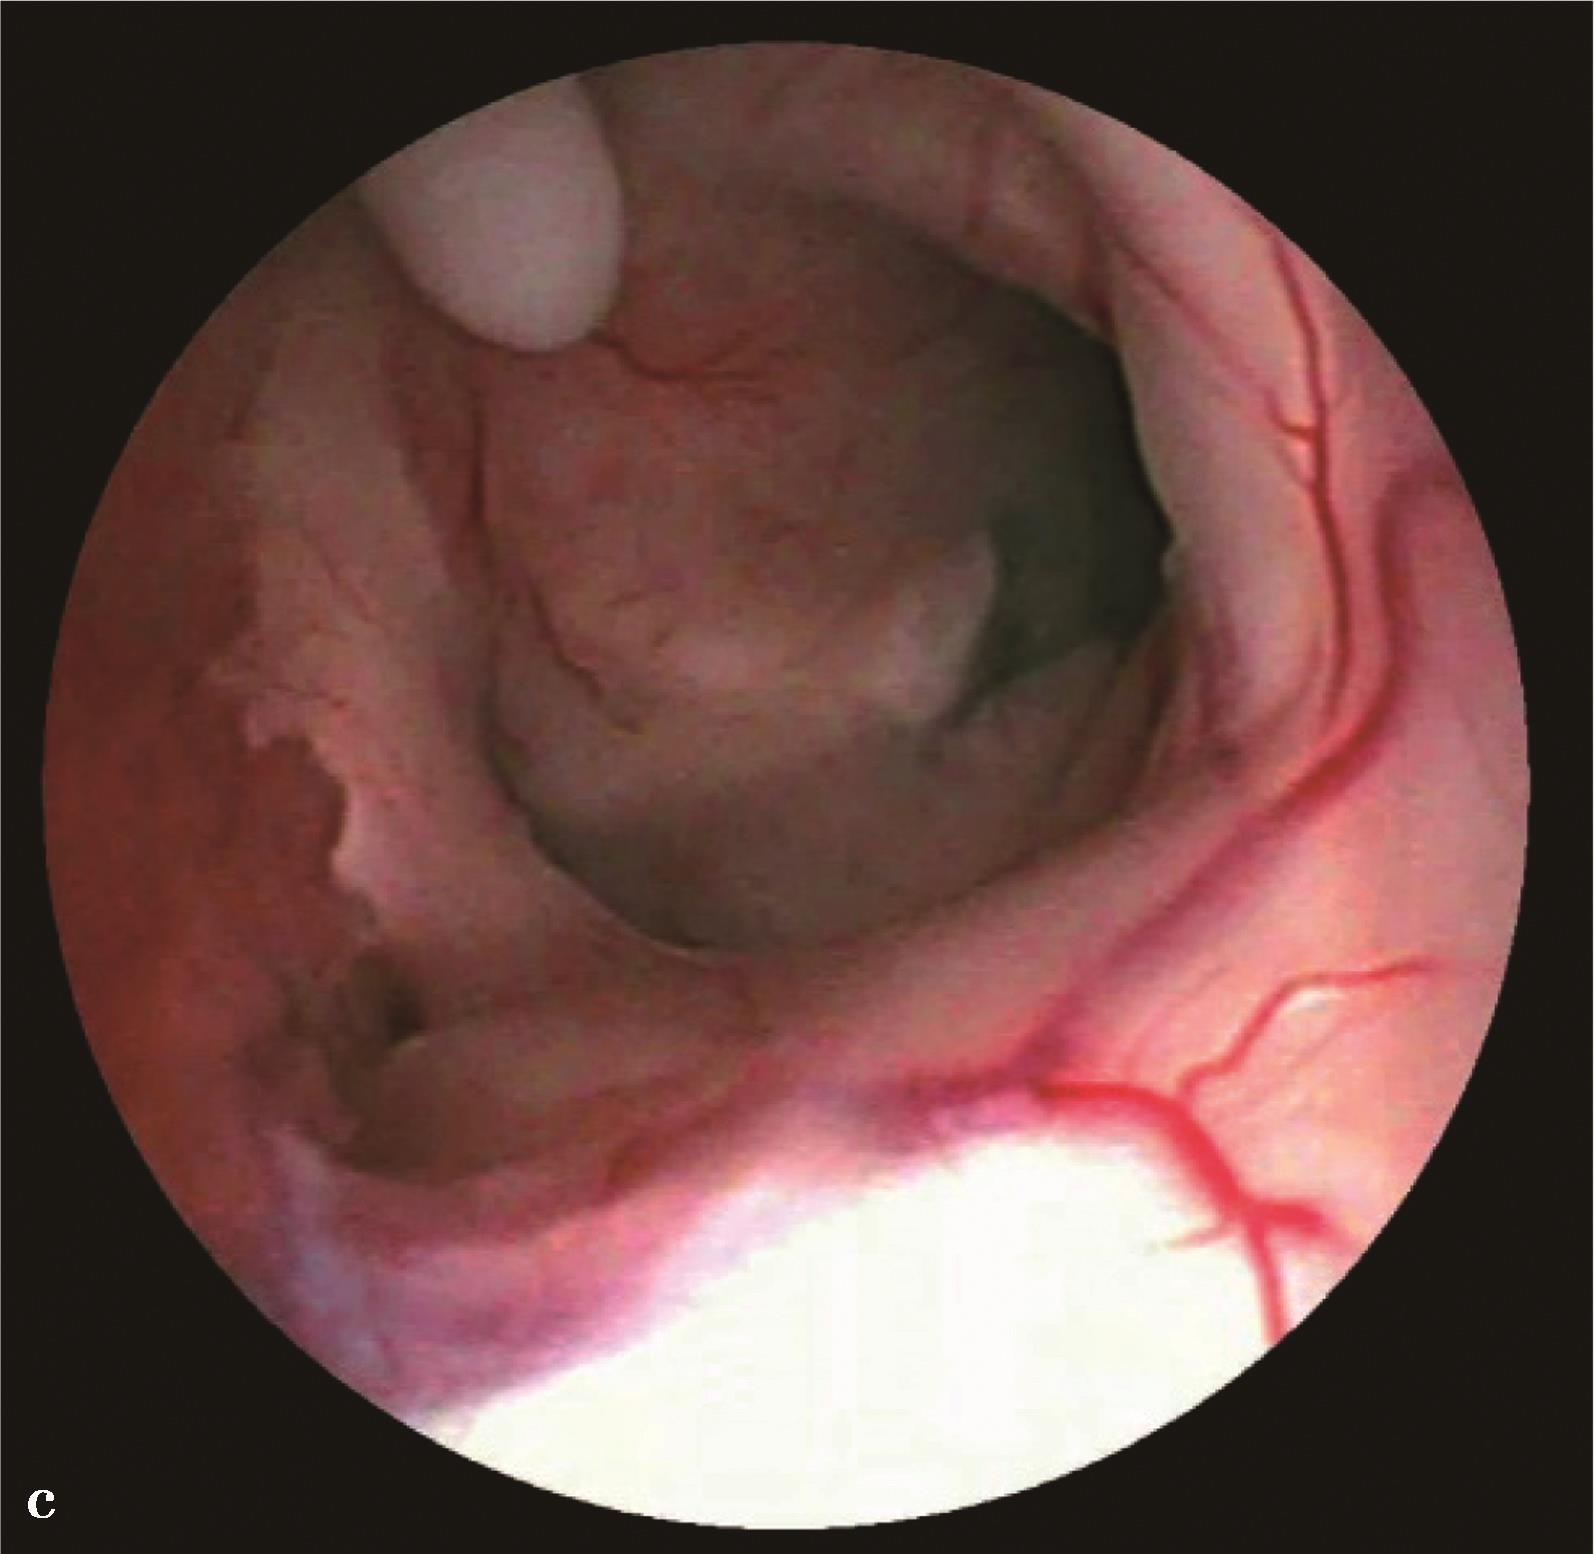

9.脑室内多发分隔型复杂脑积水(complex multiloculated hydrocephalus)首选内镜下脑室内分隔造瘘,使多房型脑积水变成单房型脑积水,酌情进行第三脑室造瘘术或脑脊液分流手术治疗(图3-1-2-10)。

图3-1-2-10 脑室内多发分隔型复杂脑积水

a.MRI矢状位片示脑室内多发分隔;b.分流术后,CT显示脑室内多发分隔;c.脑室出血继发感染后,MRI显示脑室内多发分隔